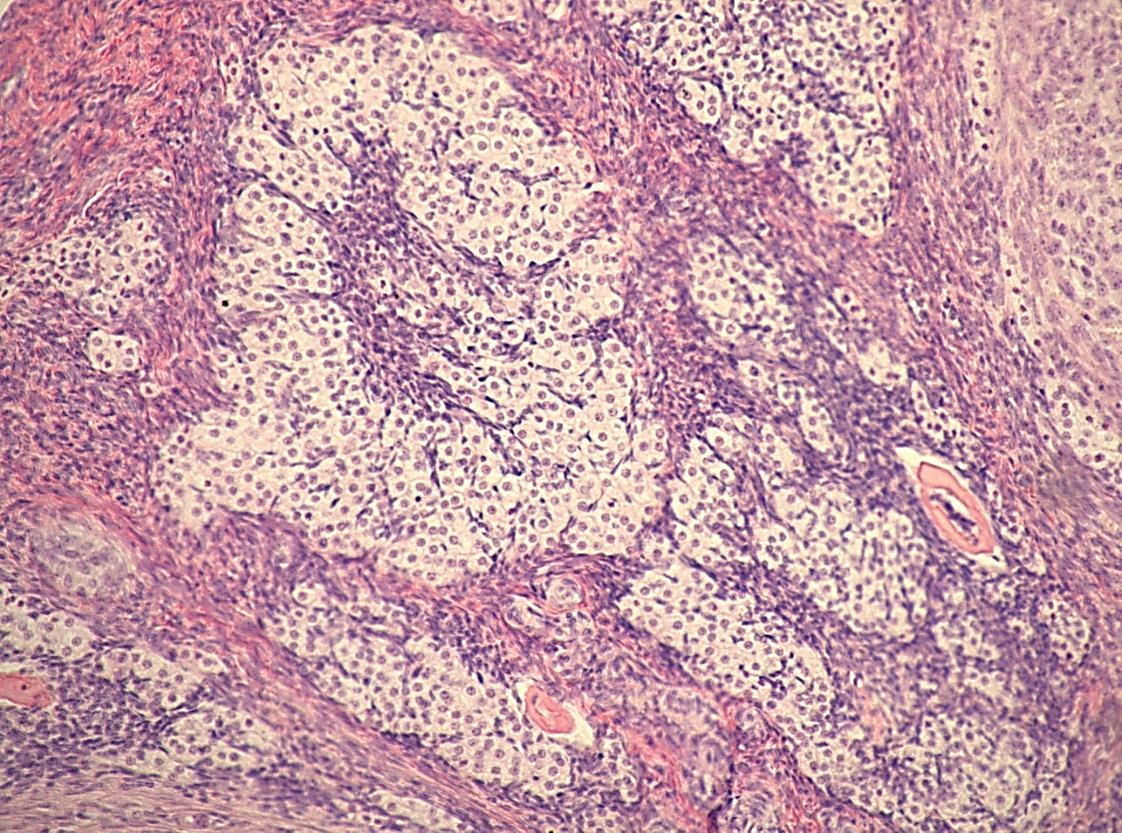

Гистологические изображения фолликулярной кисты яичника